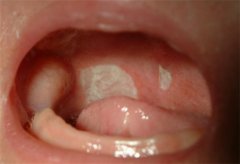

鹅口疮又称雪口病、白色念珠菌病,是由真菌传染,在粘膜表面形成白色斑膜的疾病,多见于婴幼儿(口腔不清洁、营养不良)。

鹅口疮的主要表现是在婴幼儿口腔粘膜及或舌面覆盖白色凝乳块样的小点或片状物,不易擦去,白斑周围多无红肿。